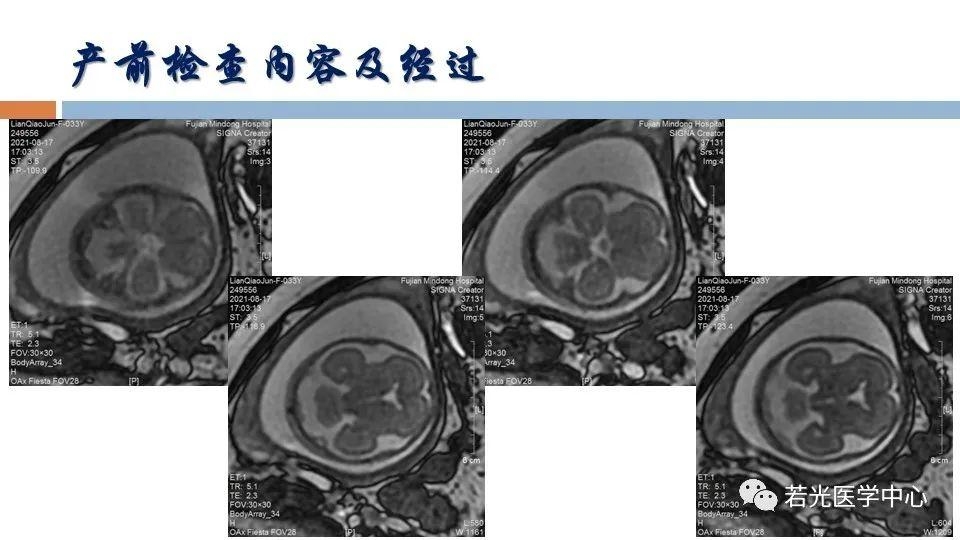

(6)表型-征象-分子遗传联合分析,遗传咨询分析与分子诊断。产前胎儿影像(超声,MRI)等异常,各类胎儿先天畸形与出生缺陷表型-基因-家系遗传分析,产前产后胎儿异常分析咨询,生育健康咨询。